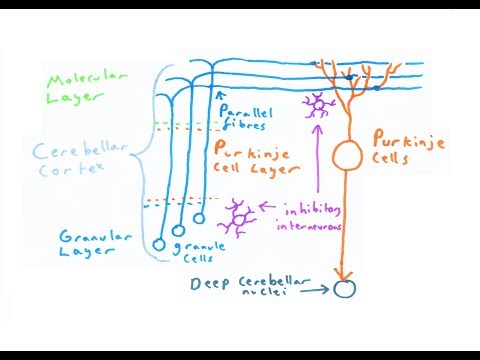

In this lecture Professor Zach Murphy will be discussing the CEREBELLUM! We will talk about the many structures involved in both the anatomy and physiology of the cerebellum. We begin our lecture by learning about cerebellum structural anatomy, followed by functional anatomy, and giving a brief overview on the deep cerebellar nuclei. We then take you to the cellular level where we show the layers of the cerebellar cortex and how information is coming in and going out. We hope you enjoy this lecture and be sure to support us below!

In this lecture Professor Zach Murphy will be discussing the CEREBELLUM! We will talk about the many structures involved in both the anatomy and physiology of the cerebellum. We begin our lecture by learning about cerebellum structural anatomy, followed by functional anatomy, and giving a brief overview on the deep cerebellar nuclei. We then take you to the cellular level where we show the layers of the cerebellar cortex and how information is coming in and going out. We hope you enjoy this lecture and be sure to support us below!